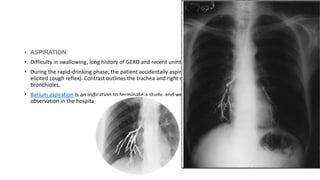

• Difficulty in swallowing, long history of GERD and recent unintentional loss of weight.

• During the rapid-drinking phase, the patient accidentally aspirated a small amount of barium (without any

elicited cough reflex). Contrast outlines the trachea and right main bronchus and smaller amount reached

bronchioles.

• Barium aspiration is an indication to terminate a study, and we sent the patient to be under close

observation in the hospital for 24 hours.